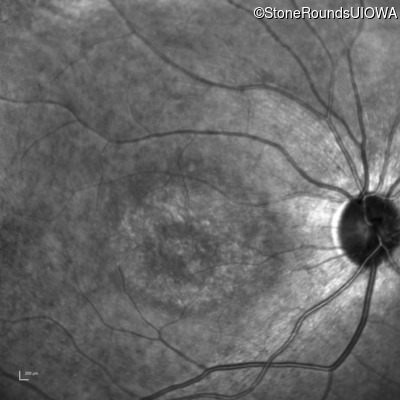

AR Stargardt Disease (IIA)

AR Stargardt Disease (IIA)

| Age at visit: 12 years |

| Age at visit: 13 years |

| Age at visit: 15 years |